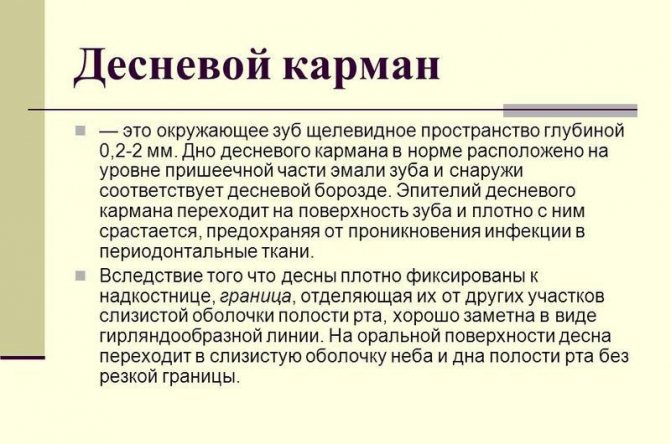

Класифікація ясенних кишень

У нормі ясна щільно прилягає до зубів на всьому протязі. В області шийки зуба ясна лежить кілька вільніше, трохи відстаючи від зуба, утворюючи нормальну десневую борозну. Глибина її не повинна бути більше 3 мм. Вимірюють глибину за допомогою спеціального інструменту – зонда з тупим кінцем, який обережно занурюють в проміжок між яснами і зубом.